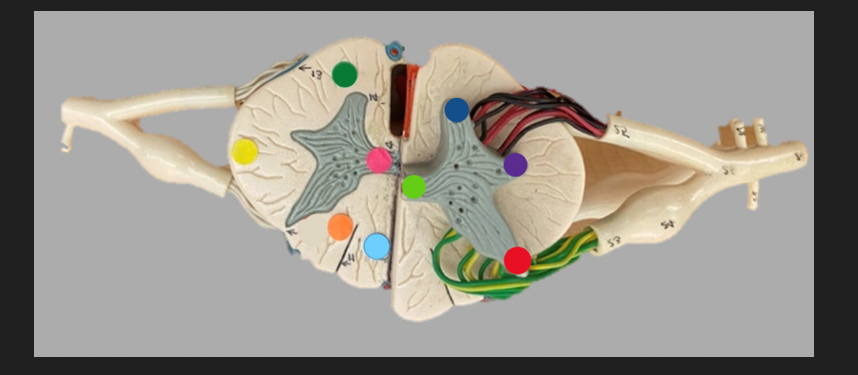

green dot

spinal nerve

orange dot

ventral root

pink dot

dorsal root

blue dot

dorsal root ganglion

red dot

dorsal ramus

yellow dot

ventral ramus

purple dot

anterior median fissure

red dot

posterior (dorsal) horn

purple dot

lateral horn

dark blue dot

anterior (ventral) horn

orange dot

dorsal column

yellow dot

lateral column

dark green

anterior column

line green and pink doit

gray commissure

light blue dot

posterior median sulcus